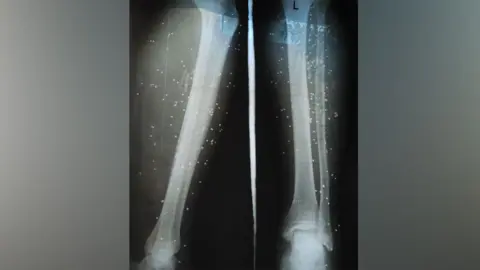

A recent short film featuring Devendra, a farmer who lost a leg to a snakebite, sheds light on the emotional and physical toll of these incidents. I went to the hospital four days after I was bitten when the pain became unbearable. But the delay cost me my leg, he reflects, emphasizing the critical importance of timely medical intervention.